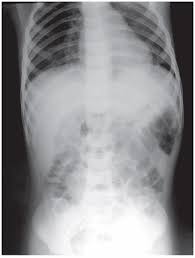

La mayoría de las lesiones graves se diagnostican por la semiología y con una simple radiología de tórax ya que las más comunes son las pleuropulmonares, siendo por suerte sumamente infrecuentes las lesiones de corazón y grandes vasos.

Las lesiones con Peligro Inminente para la vida: Obstrucción de la vía aérea, Neumotórax a tensión, Neumotórax abierto, Tórax inestable, Taponamiento cardíaco, Hemotórax masivo.